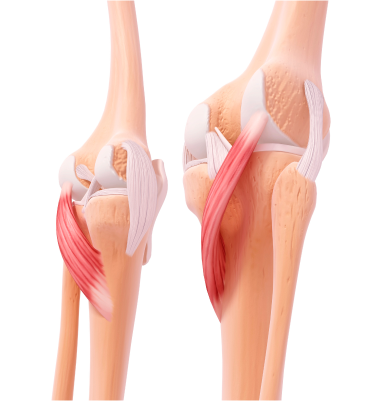

무릎 관절 내 충격을 흡수하는 반달 모양의 연골인 반월상연골이 찢어진 질환

무릎이 회전하거나 갑자기 꺾이는 움직임 중에 반월상연골에 무리가 가면서 손상이 발생하며 스포츠 외상이나 노화로 인한 연골의 퇴행성 변화로 발생합니다.

외부 충격이나 과도한 움직임으로 인해 무릎 관절의 인대가 늘어나거나 찢어지는 질환

주로 스포츠 활동 중 갑작스러운 방향 전환, 점프 착지, 외부 충격 등으로 발생합니다. 일상생활 중 무릎을 비트는 동작이나 넘어짐 등도 원인이 될 수 있습니다.